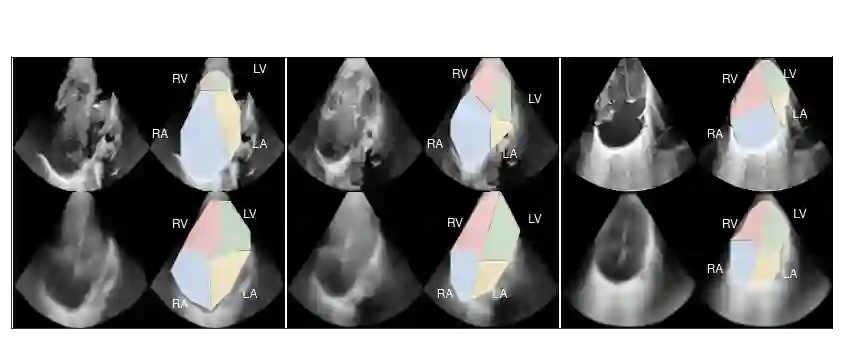

We propose a novel anomaly detection method for echocardiogram videos. The introduced method takes advantage of the periodic nature of the heart cycle to learn different variants of a variational latent trajectory model (TVAE). The models are trained on the healthy samples of an in-house dataset of infant echocardiogram videos consisting of multiple chamber views to learn a normative prior of the healthy population. During inference, maximum a posteriori (MAP) based anomaly detection is performed to detect out-of-distribution samples in our dataset. The proposed method reliably identifies severe congenital heart defects, such as Ebstein's Anomaly or Shonecomplex. Moreover, it achieves superior performance over MAP-based anomaly detection with standard variational autoencoders on the task of detecting pulmonary hypertension and right ventricular dilation. Finally, we demonstrate that the proposed method provides interpretable explanations of its output through heatmaps which highlight the regions corresponding to anomalous heart structures.